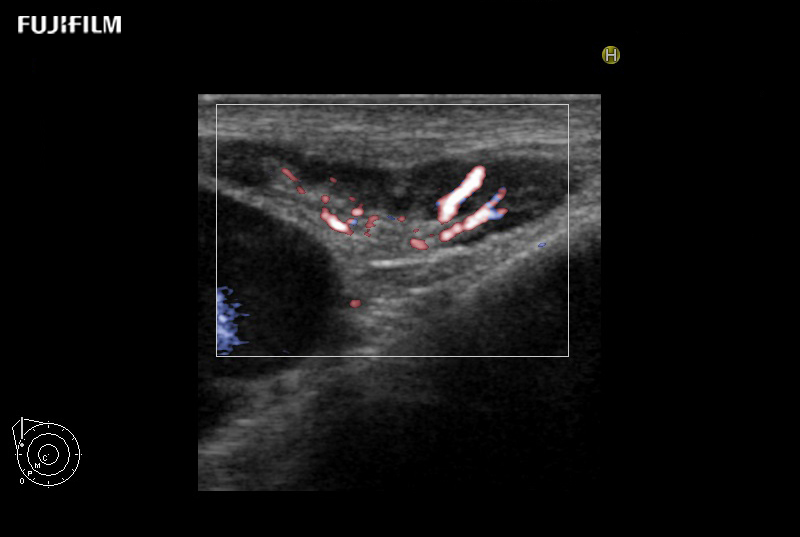

Liver Ablation Procedure using L44K

Linear array side-fire “T” transducer for open surgical procedures, providing exceptional near and far-field resolution.